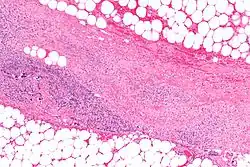

Necrotizing enzymes destroy cells and tissue. One of the best known examples is an exoenzyme produced by Streptococcus pyogenes that causes necrotizing fasciitis in humans.